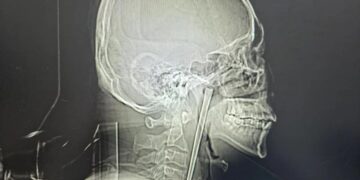

Drunkard spent 8 years with metal chopstick stuck in his throat